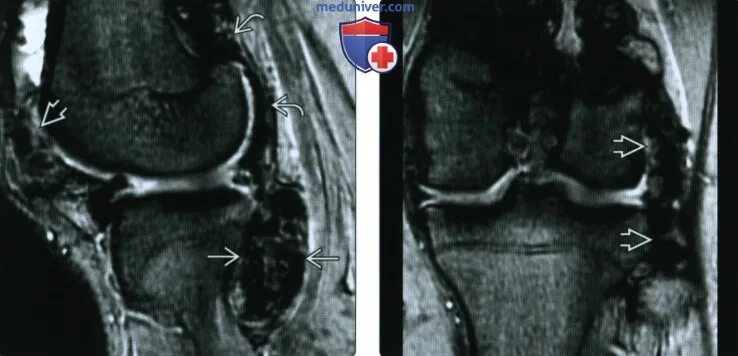

Что такое синовит коленного сустава на мрт